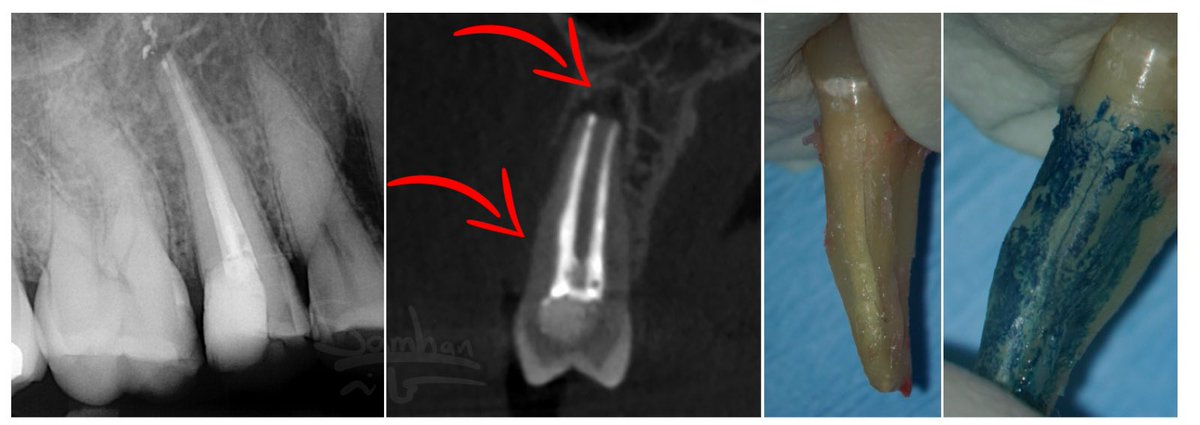

أحد أكبر التحديات اللي كنا نواجهها في تشخيص فشل علاج العصب،

إننا كنا نعتمد بشكل رئيسي على الأشعة العادية.

المشكلة إن الأشعة العادية ضعيفة جدًا في تحديد

بالضبط وين تآكل العظم اللي سببه تسرب البكتيريا.

أحيانًا يكون تآكل العظم واضح في نهاية الجذر…

لكن في حالات كثيرة، التآكل يكون في أماكن أخرى تمامًا:

• مرات يكون على جانب الجذر – بسبب قناة جانبية أو ثقب.

• مرات يكون بين الجذور Furcation

• ومرات… إذا كنا محظوظين وصار في Sinus tract،

نستخدم الـ GP لمعرفة اتجاه الخراج.

لكن حتى الـ GP ما يعطي الصورة كاملة،

لأن ممكن يكون في خراج ثاني بمكان مختلف واحنا ما ندري عنه.

وهنا كانت النقلة النوعية:

لما بدأنا نستخدم الأشعة المقطعية – CBCT،

أصبح التشخيص دقيق بشكل كبير.

معرفة مكان تآكل العظم مو بس تسهّل العلاج…

أحيانًا تغيّر خطة العلاج بالكامل.

لهذا السبب، في حالات فشل علاج العصب،

الـ CBCT مو مجرد خيار يساعد…

صار ضرورة في أغلب الحالات عشان نعالج السن بالطريقة الصحيحة.

هذه بعض الحالات اللي تبين اماكن الخراج.